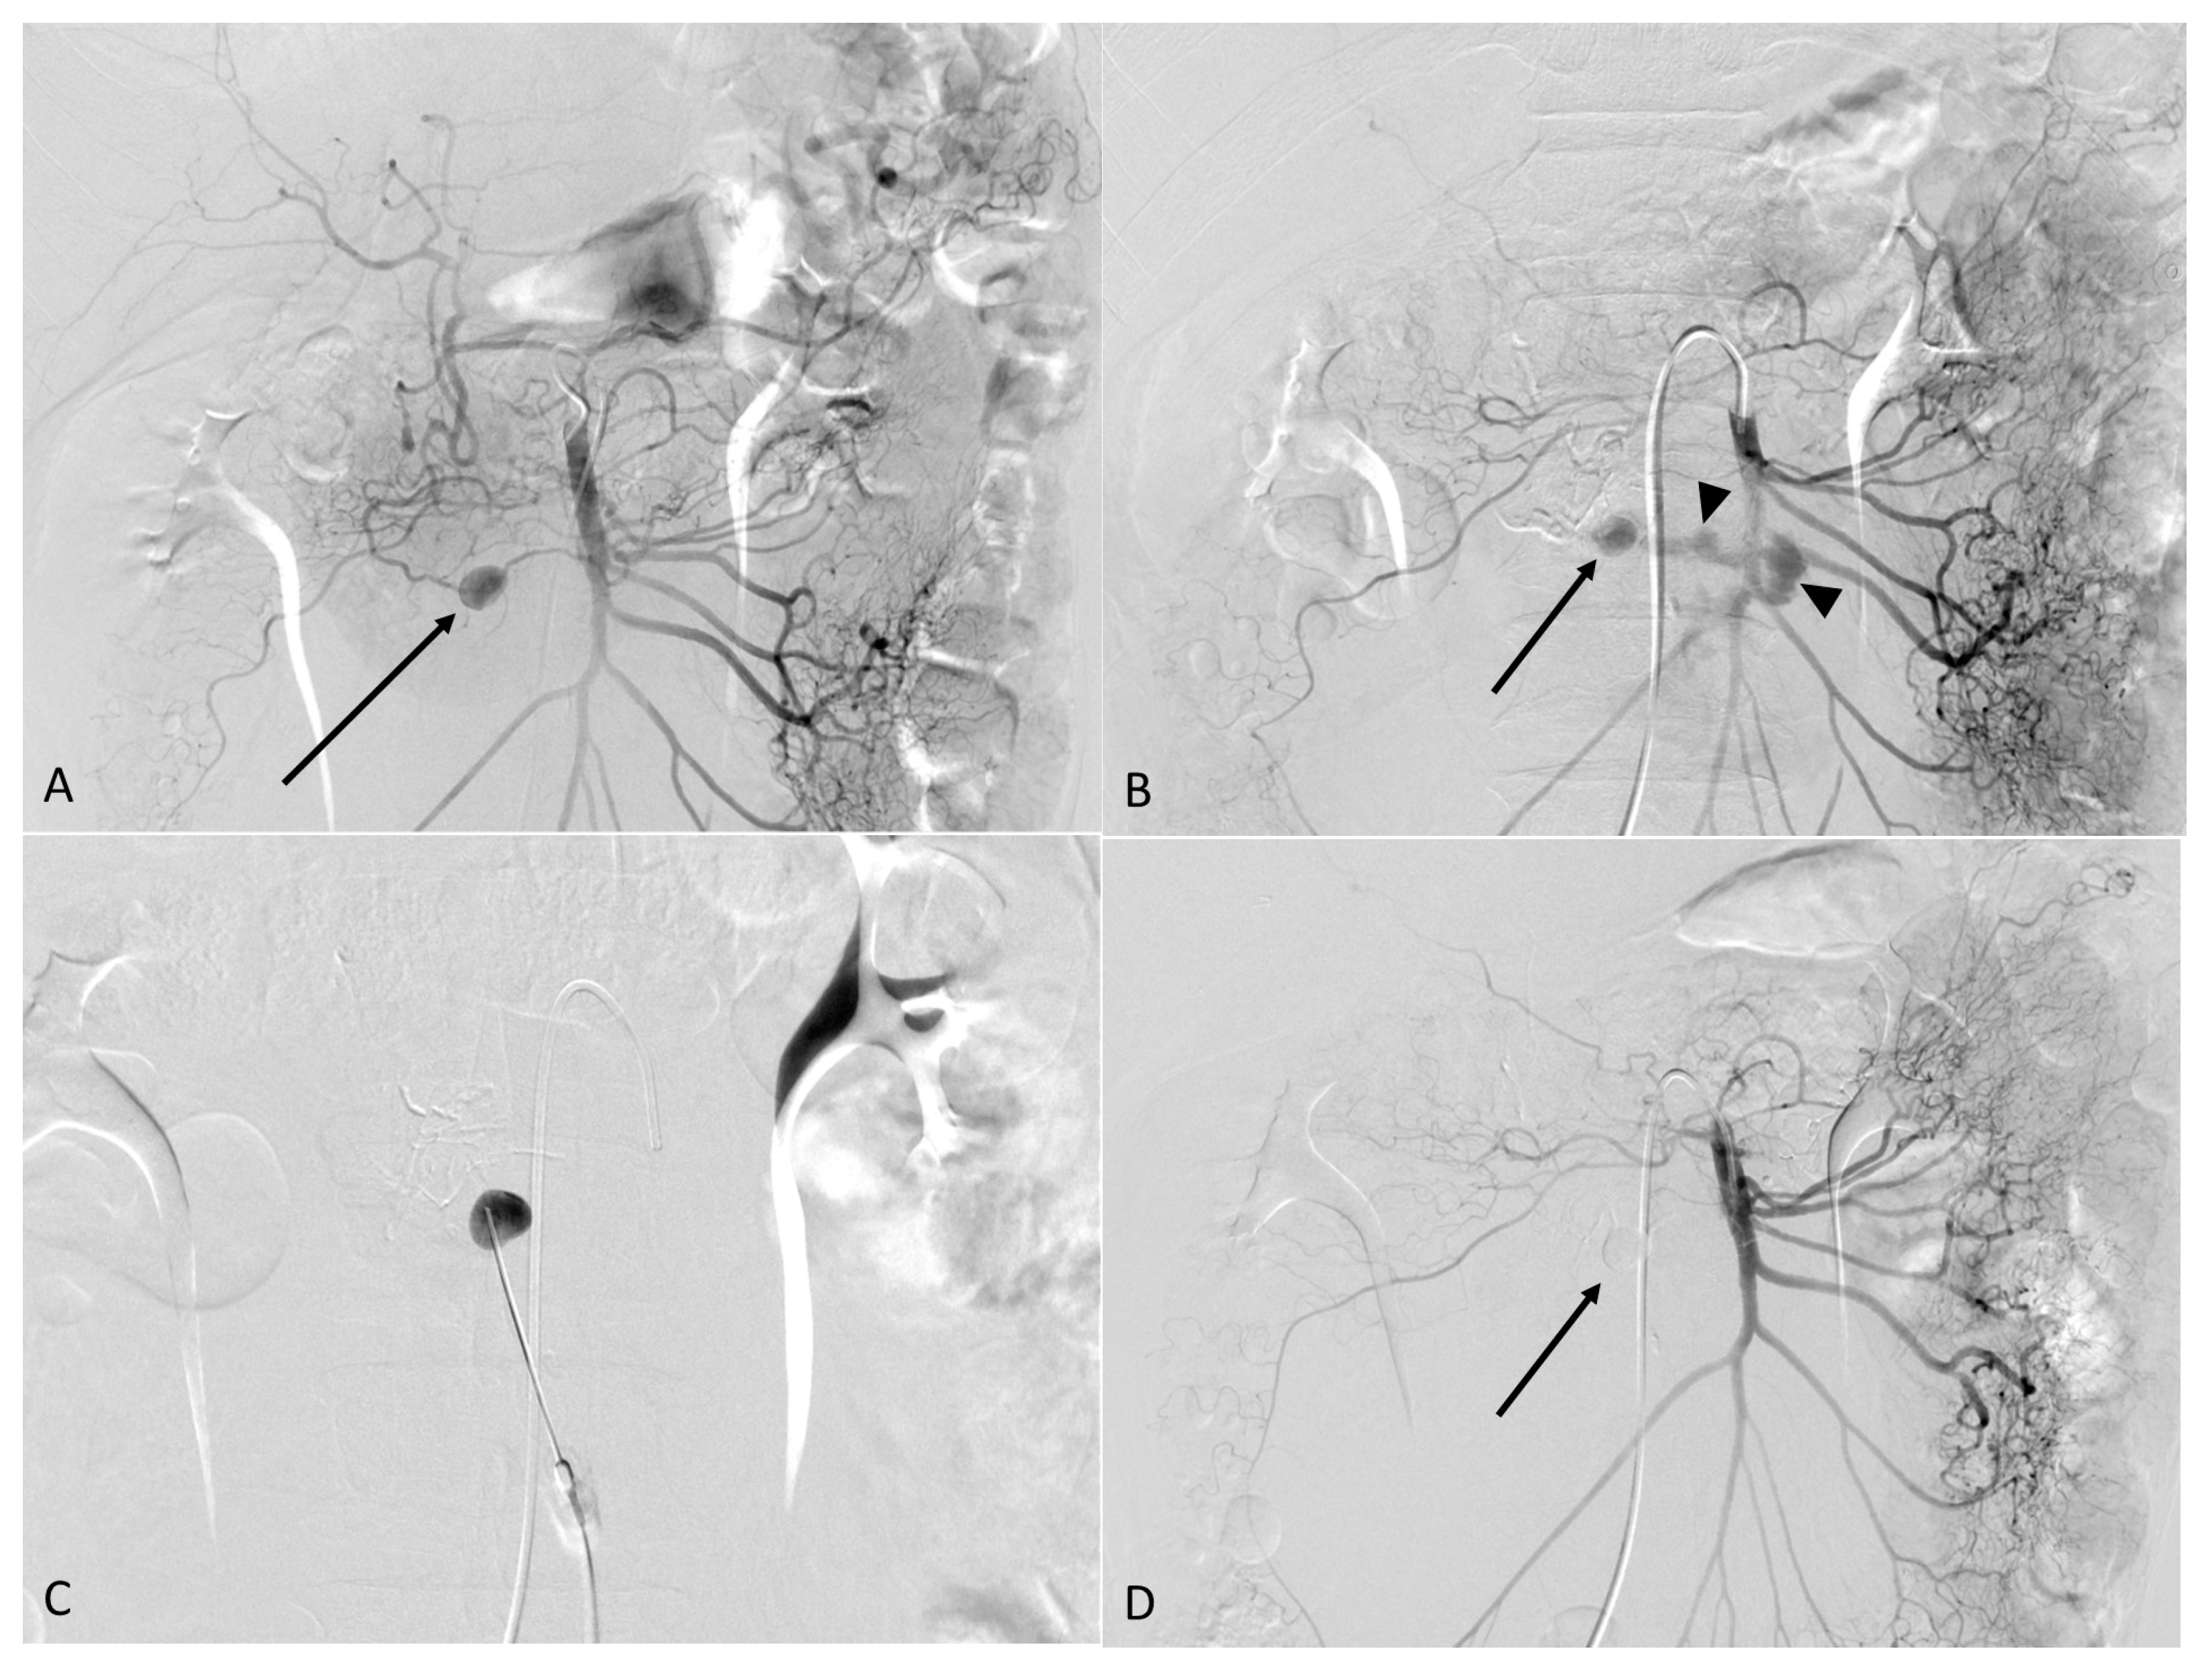

2. Case Report